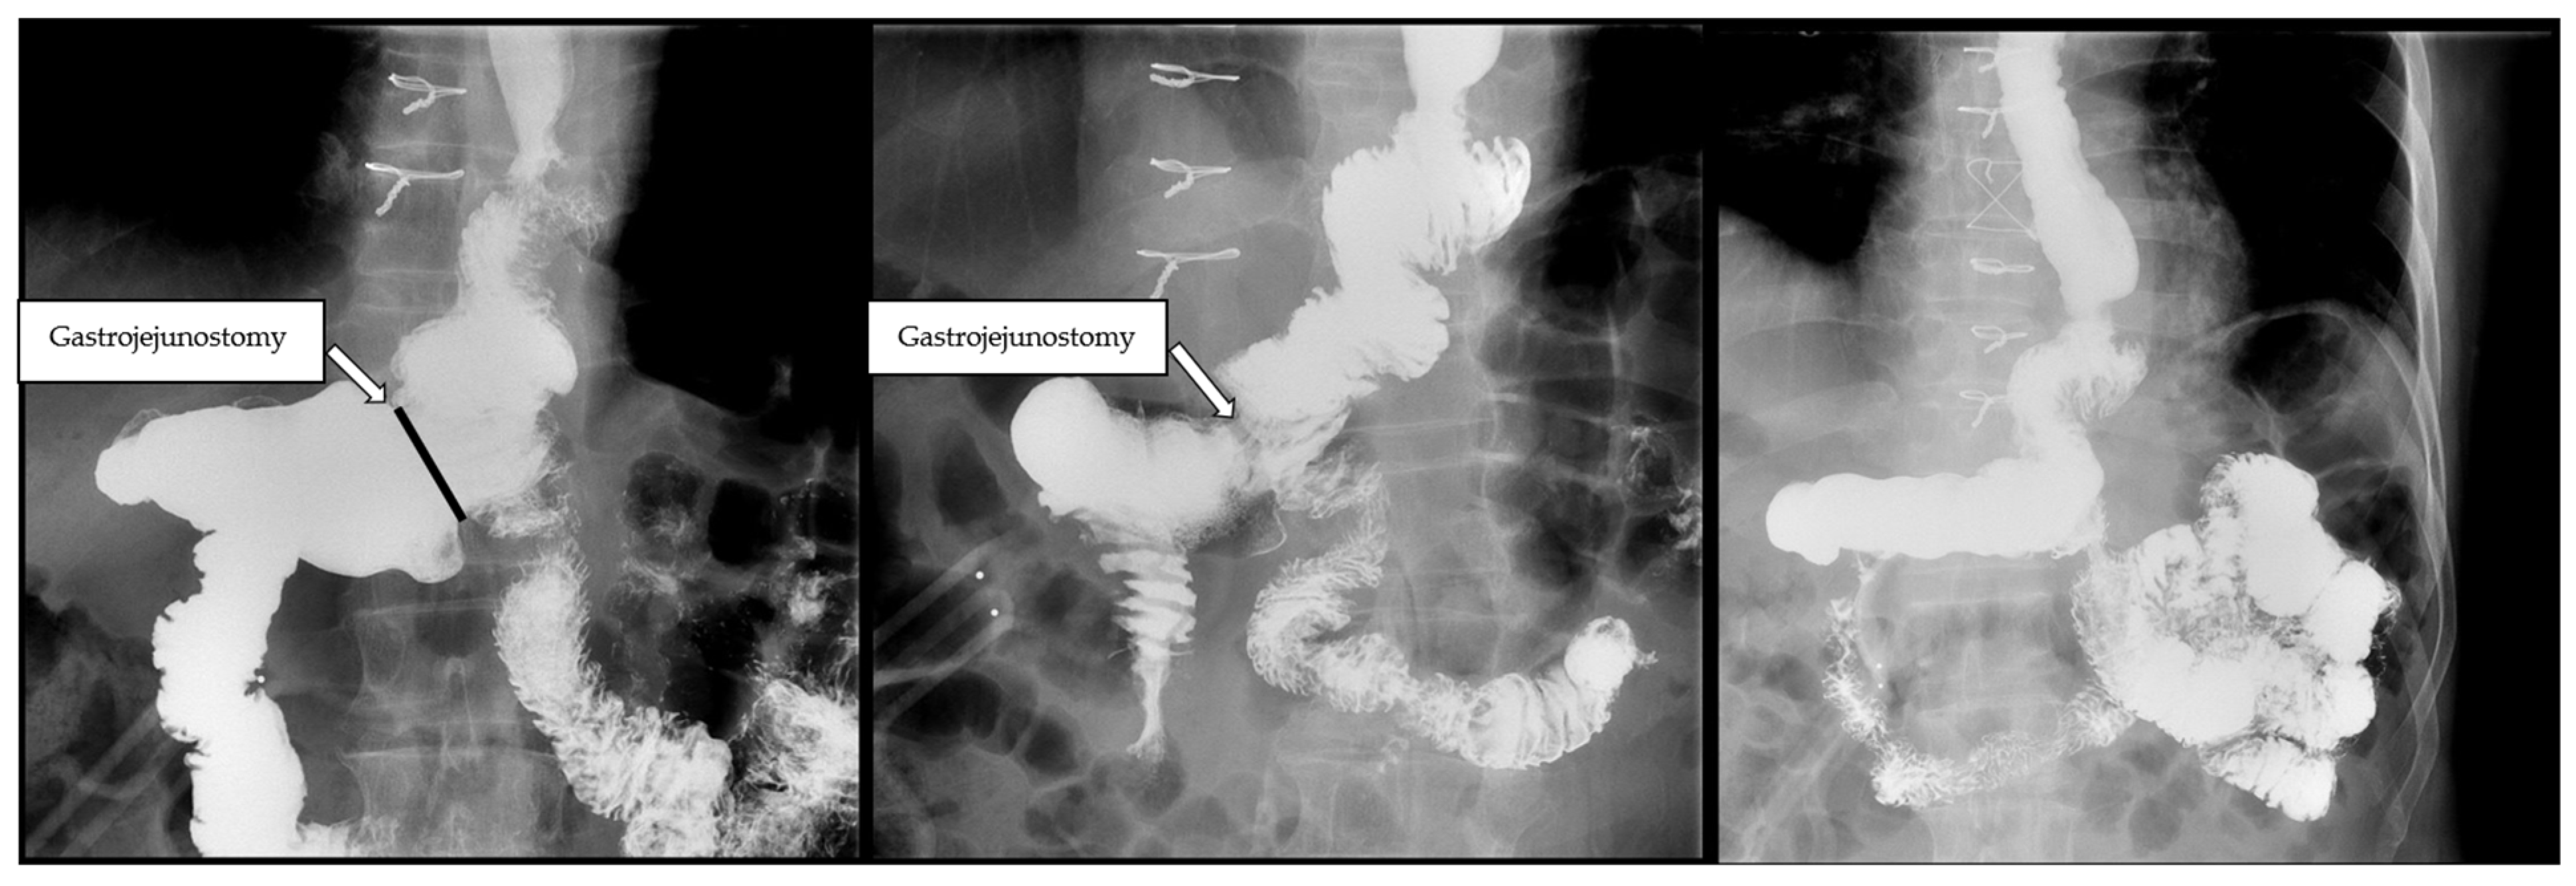

2.1. Surgical Technique